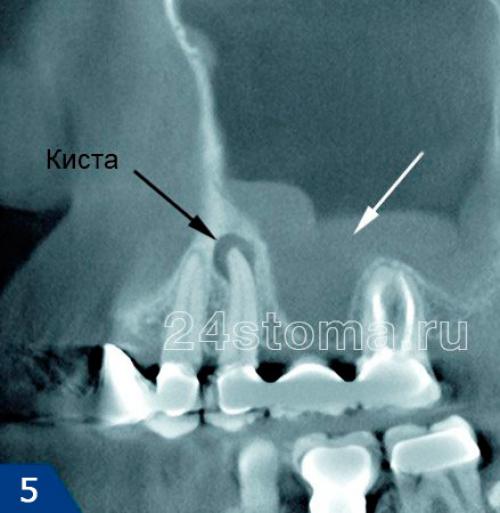

Вторая большая группа причин – это причины одонтогенного происхождения (т.е. связанные с зубами). Примерно в 32% случаев развитие верхнечелюсного синусита связано с воспалительными очагами у верхушек корней 5-6-7 зубов верхней челюсти. Дело в том, что дно верхнечелюстных пазух находится всего в 1-3 мм от верхушек корней этих зубов, и поэтому при возникновении очага воспаления у верхушки корня – воспаление может затронуть и слизистую оболочку пазух (рис.5).

Одонтогенный верхнечелюстной синусит может также развиться – 1) при ошибках при пломбировании корневых каналов, когда пломбировочный материал выводится за верхушку корня, 2) в результате проталкивания инфицированной пульпы за верхушку корня при лечении пульпита и периодонтита, 3) при возникновении перфорации верхнечелюстной пазухи, допущенной во время удаления боковых зубов верхней челюсти, 4) как осложнение при имплантации зубов в боковых отделах верхней челюсти.

Важно : у большой группы пациентов могут одновременно быть и риногенная, и одонтогенная причины развития синусита. Например, в области верхушек корней 5-6-7 верхних зубов у пациента могут быть очаги хронического воспаления, которые сами по себе не вызывали воспаления слизистой оболочки верхнечелюстных пазух. Но в случае развития ОРВИ происходит развитие не только острого насморка (затрудняющего отхождения слизистого секрета из верхнечелюстных пазух), но и активизация воспалительных очагов в области верхушек корней зубов. Сочетание этих факторов во много раз повышает риск развития синусита у пациента.